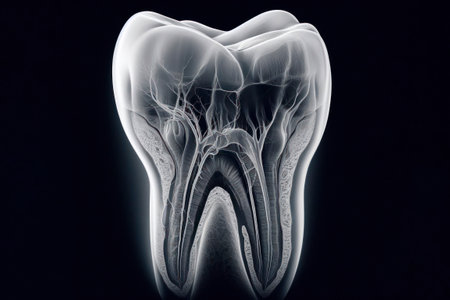

Delicate structures within a tooth illustrate dental complexity and biological function.

Anatomical model of a tooth, isolated on a black background. Perfect for dental education and healthcare presentations, showcasing tooth structure and root canals for better understanding.

Anatomical intricacy: tooth structure, nerve, with a visible cartilaginous stage, detailed layers and components of a tooth, emphasizing the complex interplay of dental anatomy

Transparent tooth model displaying detailed internal anatomy, including nerves, blood vessels, and pulp structure, isolated on a gray background.

High-Resolution 3D Tooth Model with Nerves, Roots, and Holographic Interface

AI generated 3D rendering of a translucent human tooth revealing an intricate glowing neural and vascular network in orange over a deep blue background conveying futuristic biovisual data processing

This image provides a detailed cross-section view of a human tooth, revealing the inner anatomy including the root pulp and surrounding bone structures. It is an educational and informative visual aid

An intricate view of a tooth nerve root structure, showcasing dental anatomy and emphasizing the need for preventive oral care.

Detailed cross-section of a human tooth displaying enamel, dentin, pulp, and root anatomy. Educational medical illustration on a gradient blue background.

An intricate view of a tooth nerve root structure, showcasing dental anatomy and emphasizing the need for preventive oral care.

X-ray of a human tooth. ai generative.